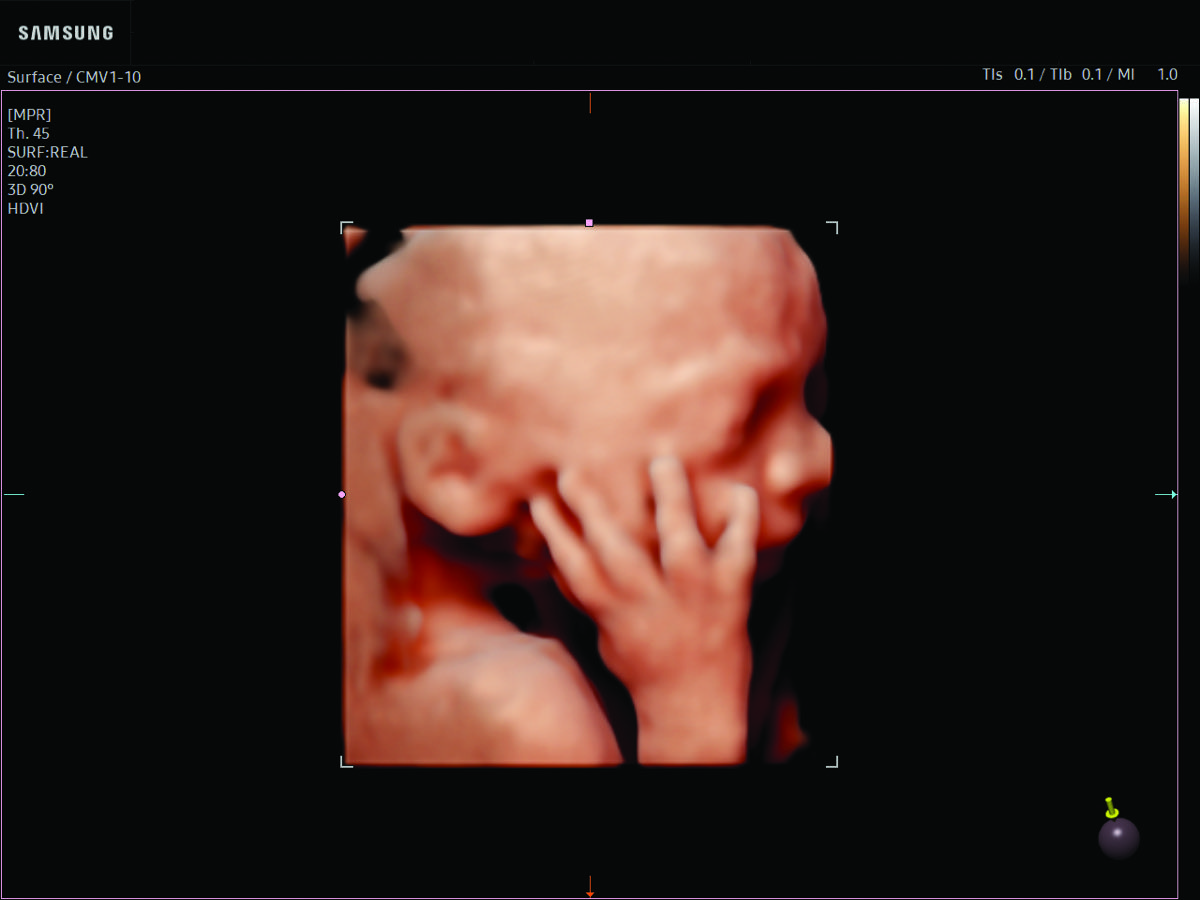

Comprehensive, advanced and expert MFM care for high-risk pregnancies